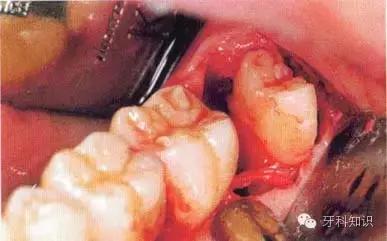

f 远中牙片取出后即可拔除近中部分。术后应注意牙槽嵴顶的高度。保留颊侧骨板很重要,它有利于牙槽窝和第二磨牙牙槽骨的完全重建

g 将皮瓣复位后,磨牙后区缝合2针,此处使用的是不可吸收的聚硅酮丝线(4—0)。第一、二磨牙之间缝合1针,以维持楔状隙内龈乳头的位置并确保迅速的愈合。轻压组织至少2 min,使骨膜和骨皮质、牙龈和牙骨质粘连复位。作用于软组织的压力还能排出气泡形成良好的血凝块

h只要有根分叉且近中倾斜程度不大、车针能够顺利进入,沿牙体长轴进行的正中切割就能顺利进行。该牙的根间孔尚未完全闭合